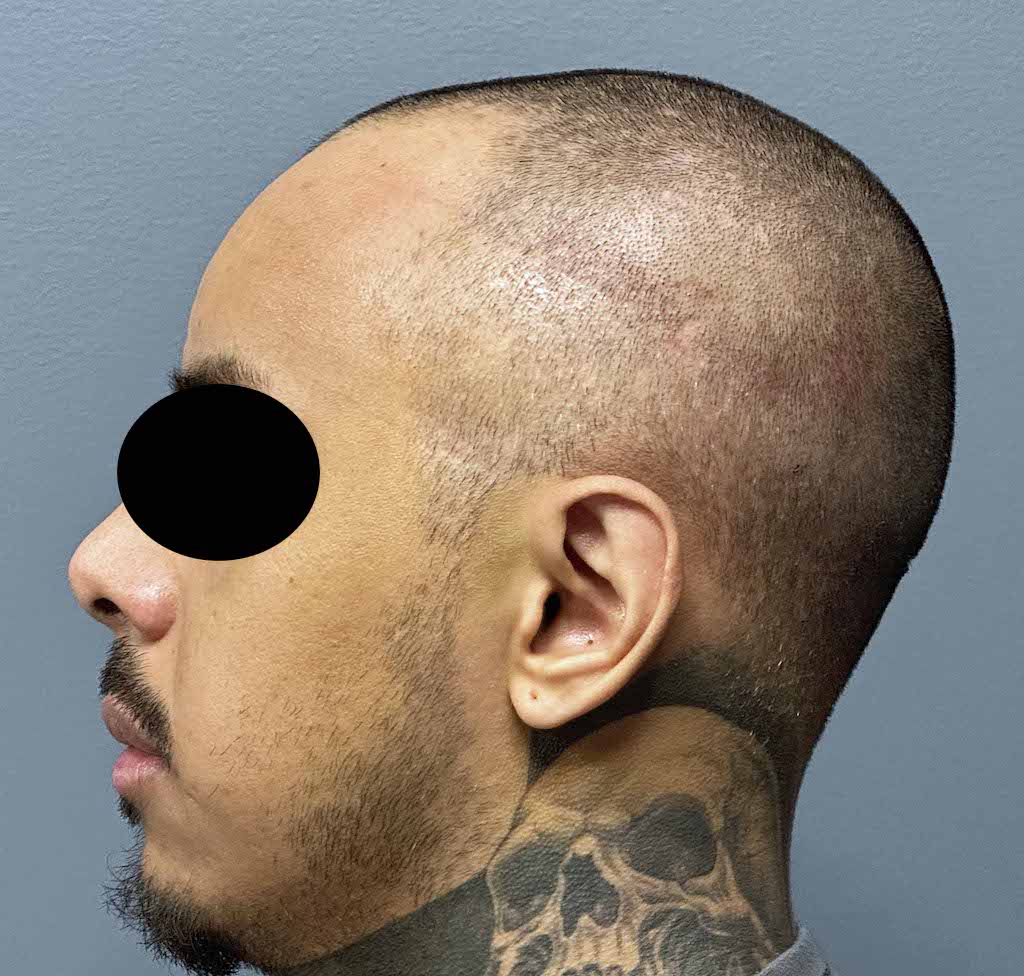

Patient 100

Desire for reshaping of an asymmetric flat back of the head in a shaved head male.

A combined back of the head reshaping procedure was done with a custom skull implant, sagittal ridge reduction and a right temporal muscle reduction.

Desire for reshaping of an asymmetric flat back of the head in a shaved head male.

A combined back of the head reshaping procedure was done with a custom skull implant, sagittal ridge reduction and a right temporal muscle reduction.